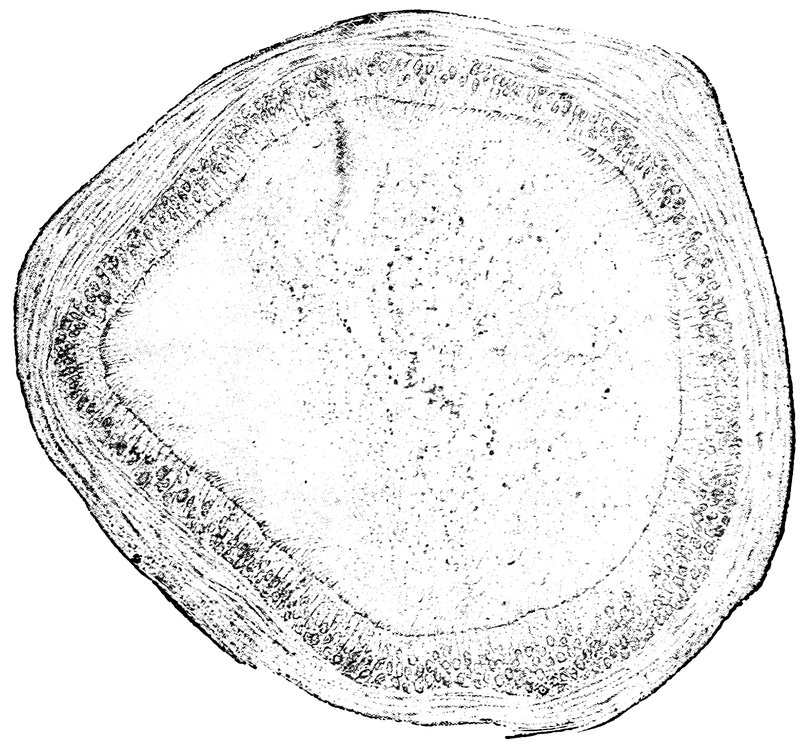

| 47. | Horizontal section through the female breast | 75 |

| 84. | Sagittal section through the ovary of a girl aged sixteen | 583 |

| 85. | Sagittal section through the ovary of a woman aged seventy-two years | 584 |

| 87. | Ovary of a Girl aged nineteen years (Normal Size) | 585 |

| 88. | Ovary of a Woman seventy-two years of age (Normal Size) | 585 |